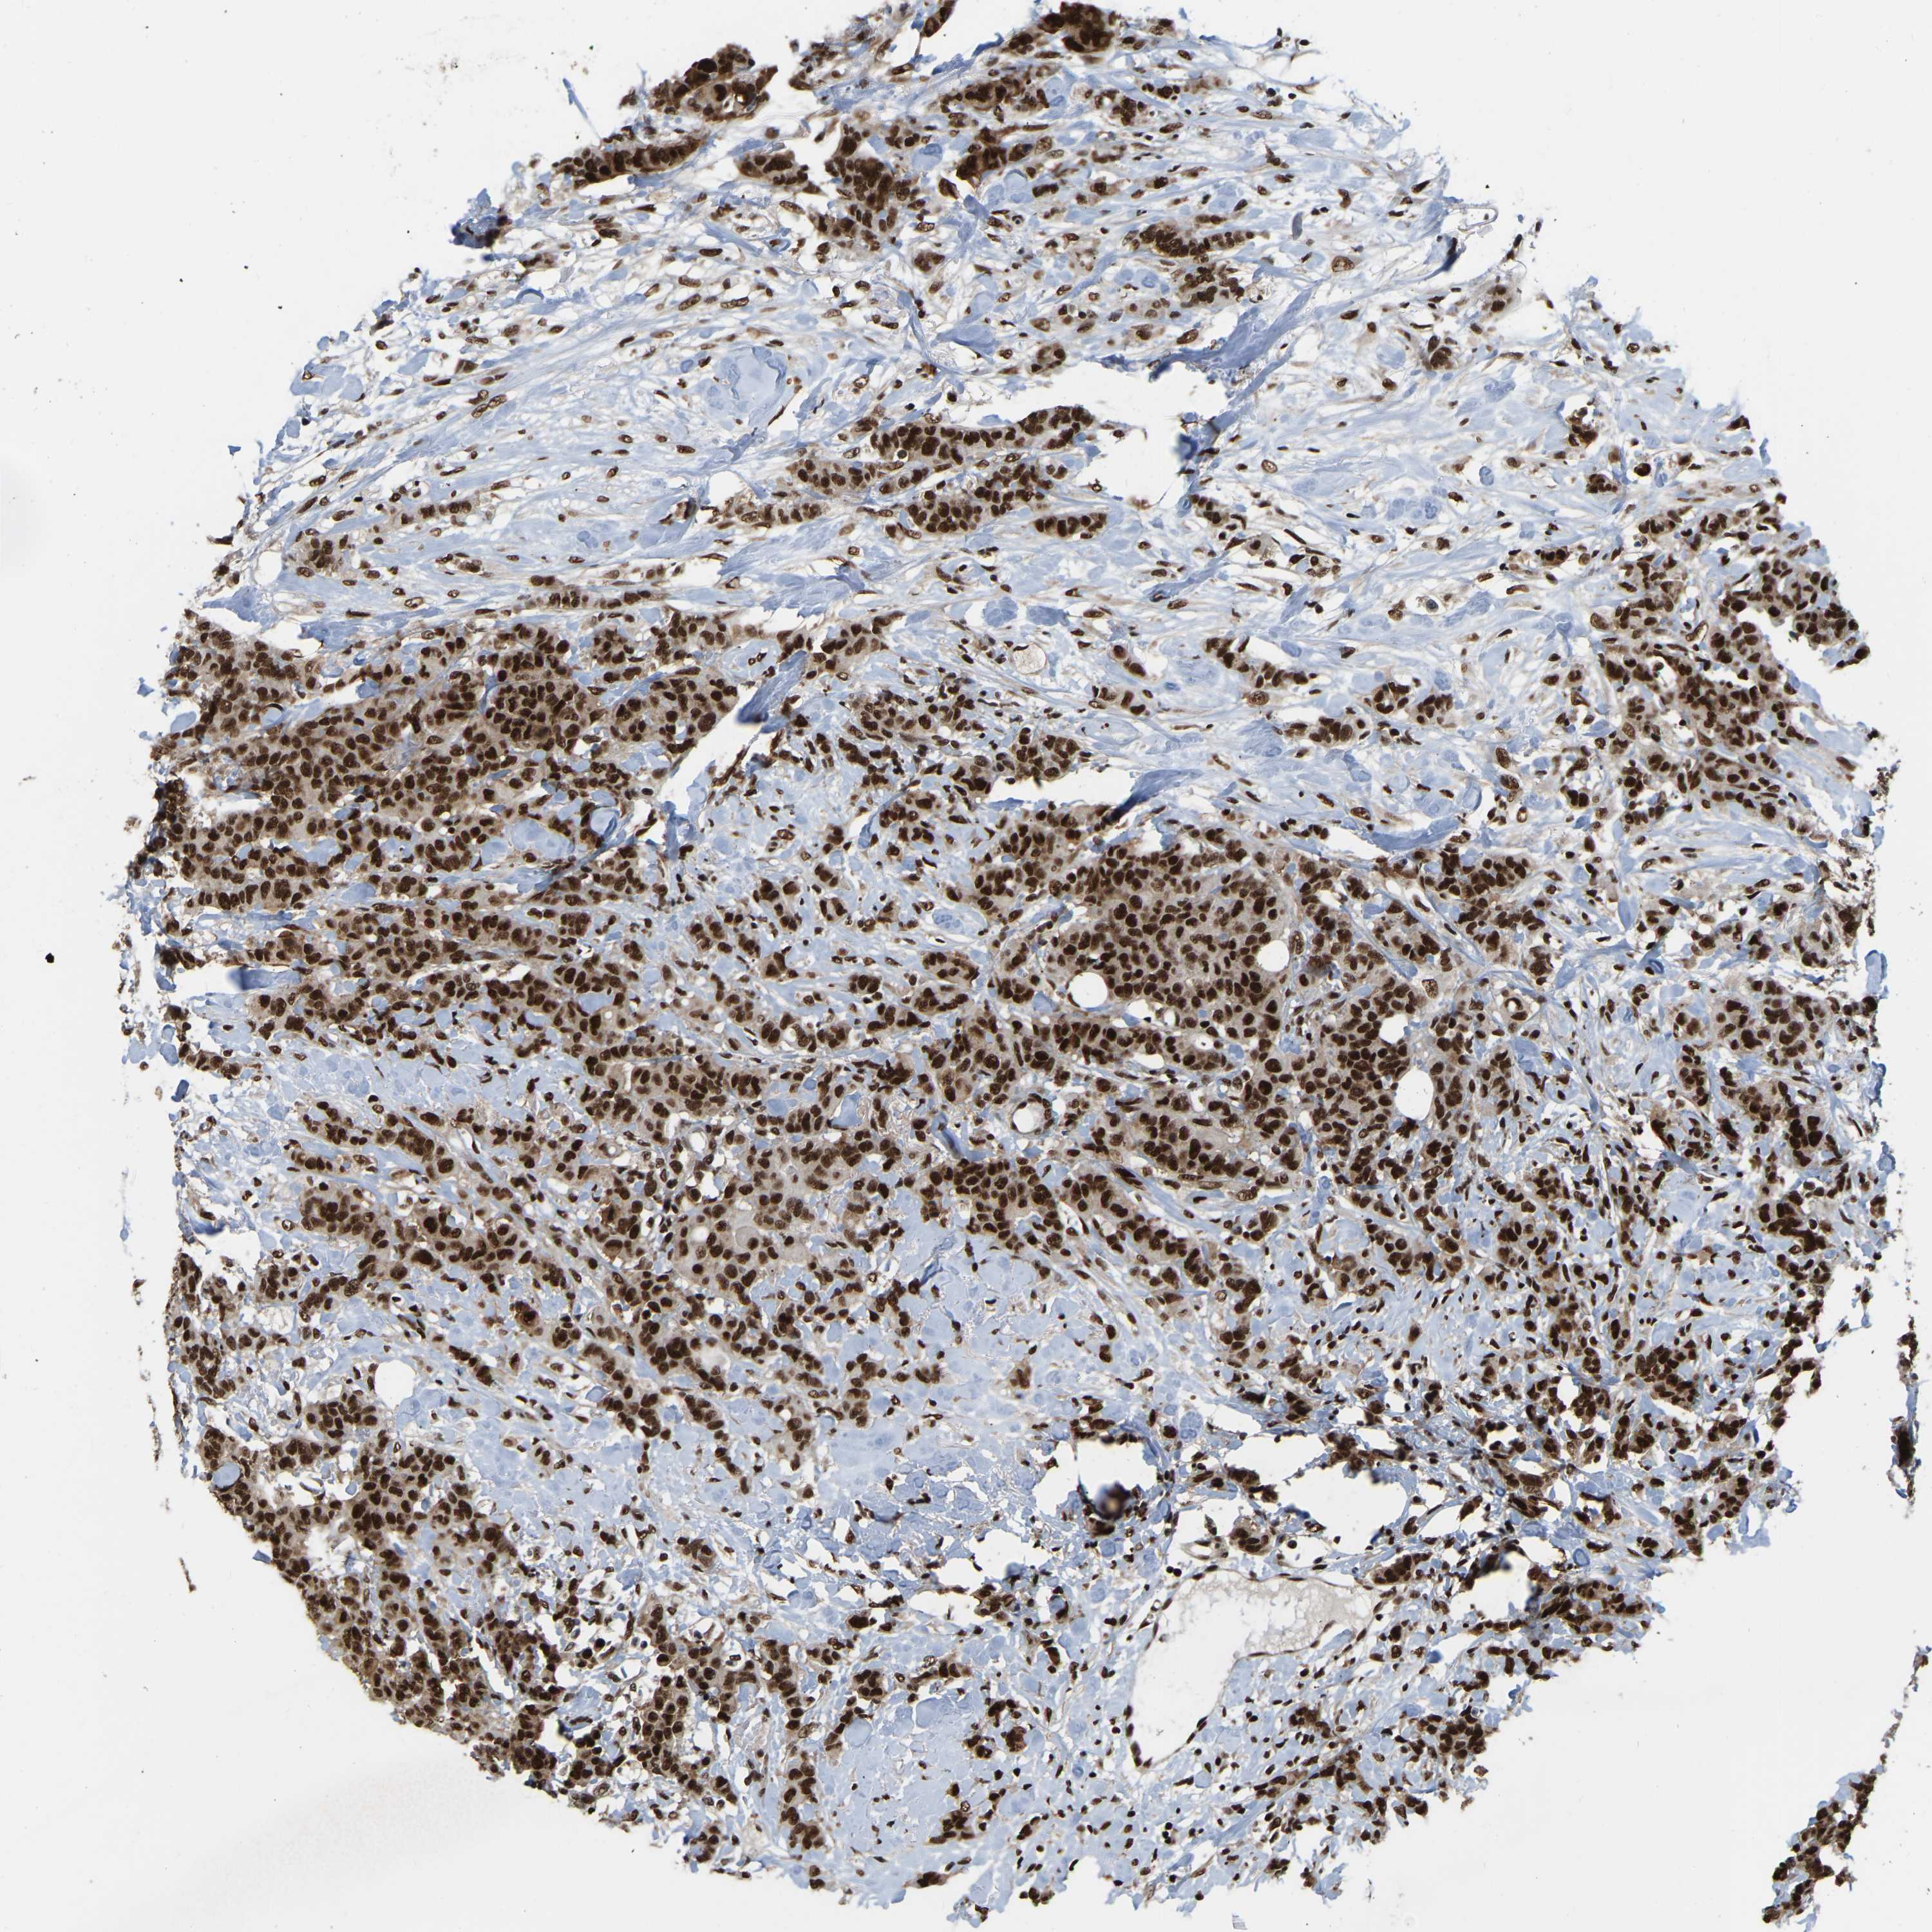

CANCER BREAST CANCER Show tissue menu

BRCA TCGA BRCA VALIDATION PROTEIN EXPRESSION

Breast cancer

Human cancer